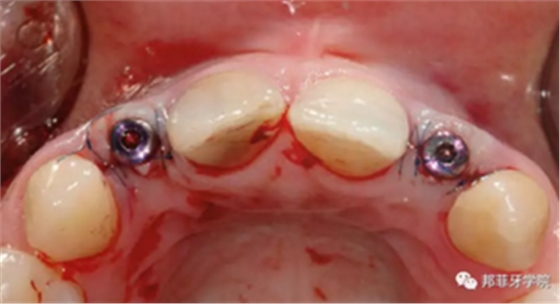

采用手術(shù)導(dǎo)板進(jìn)行備洞及植入,植入扭矩35Ncm。植體適當(dāng)偏腭側(cè)植入,避免鄰近結(jié)構(gòu)破壞及前庭處骨外壁穿孔。植體肩臺(tái)位于鄰牙釉牙本質(zhì)界根尖方2mm(圖7&8)。

圖7 & 8:導(dǎo)板下備洞及植入

牙齦成型器周圍應(yīng)嚴(yán)密縫合,防止唾液進(jìn)入切口(圖9)。X線片顯示植體位置理想(圖10)。愈合期未見并發(fā)癥,植體周圍牙齦愈合良好(圖11)。十周后取模,椅旁制備臨時(shí)牙(圖12),并制作螺絲固位PEEK基臺(tái)。

圖 9:上牙齦成形器并嚴(yán)密縫合